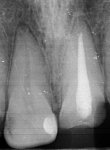

Ходил 2 года по врачам, говорю зуб без нерва болит, в ответ - у тебя все збс, выдумываешь. Сходил в платку к студенту, он обнаружил огромную кариозную полость между зубами, зуб без нерва уже с кистой, а соседний полностью пульпитный.

2323.jpg

Аноны, добрый вечер.

Посоветуйте пасту зубную после пломбирования и чистки от камня передних зубов.